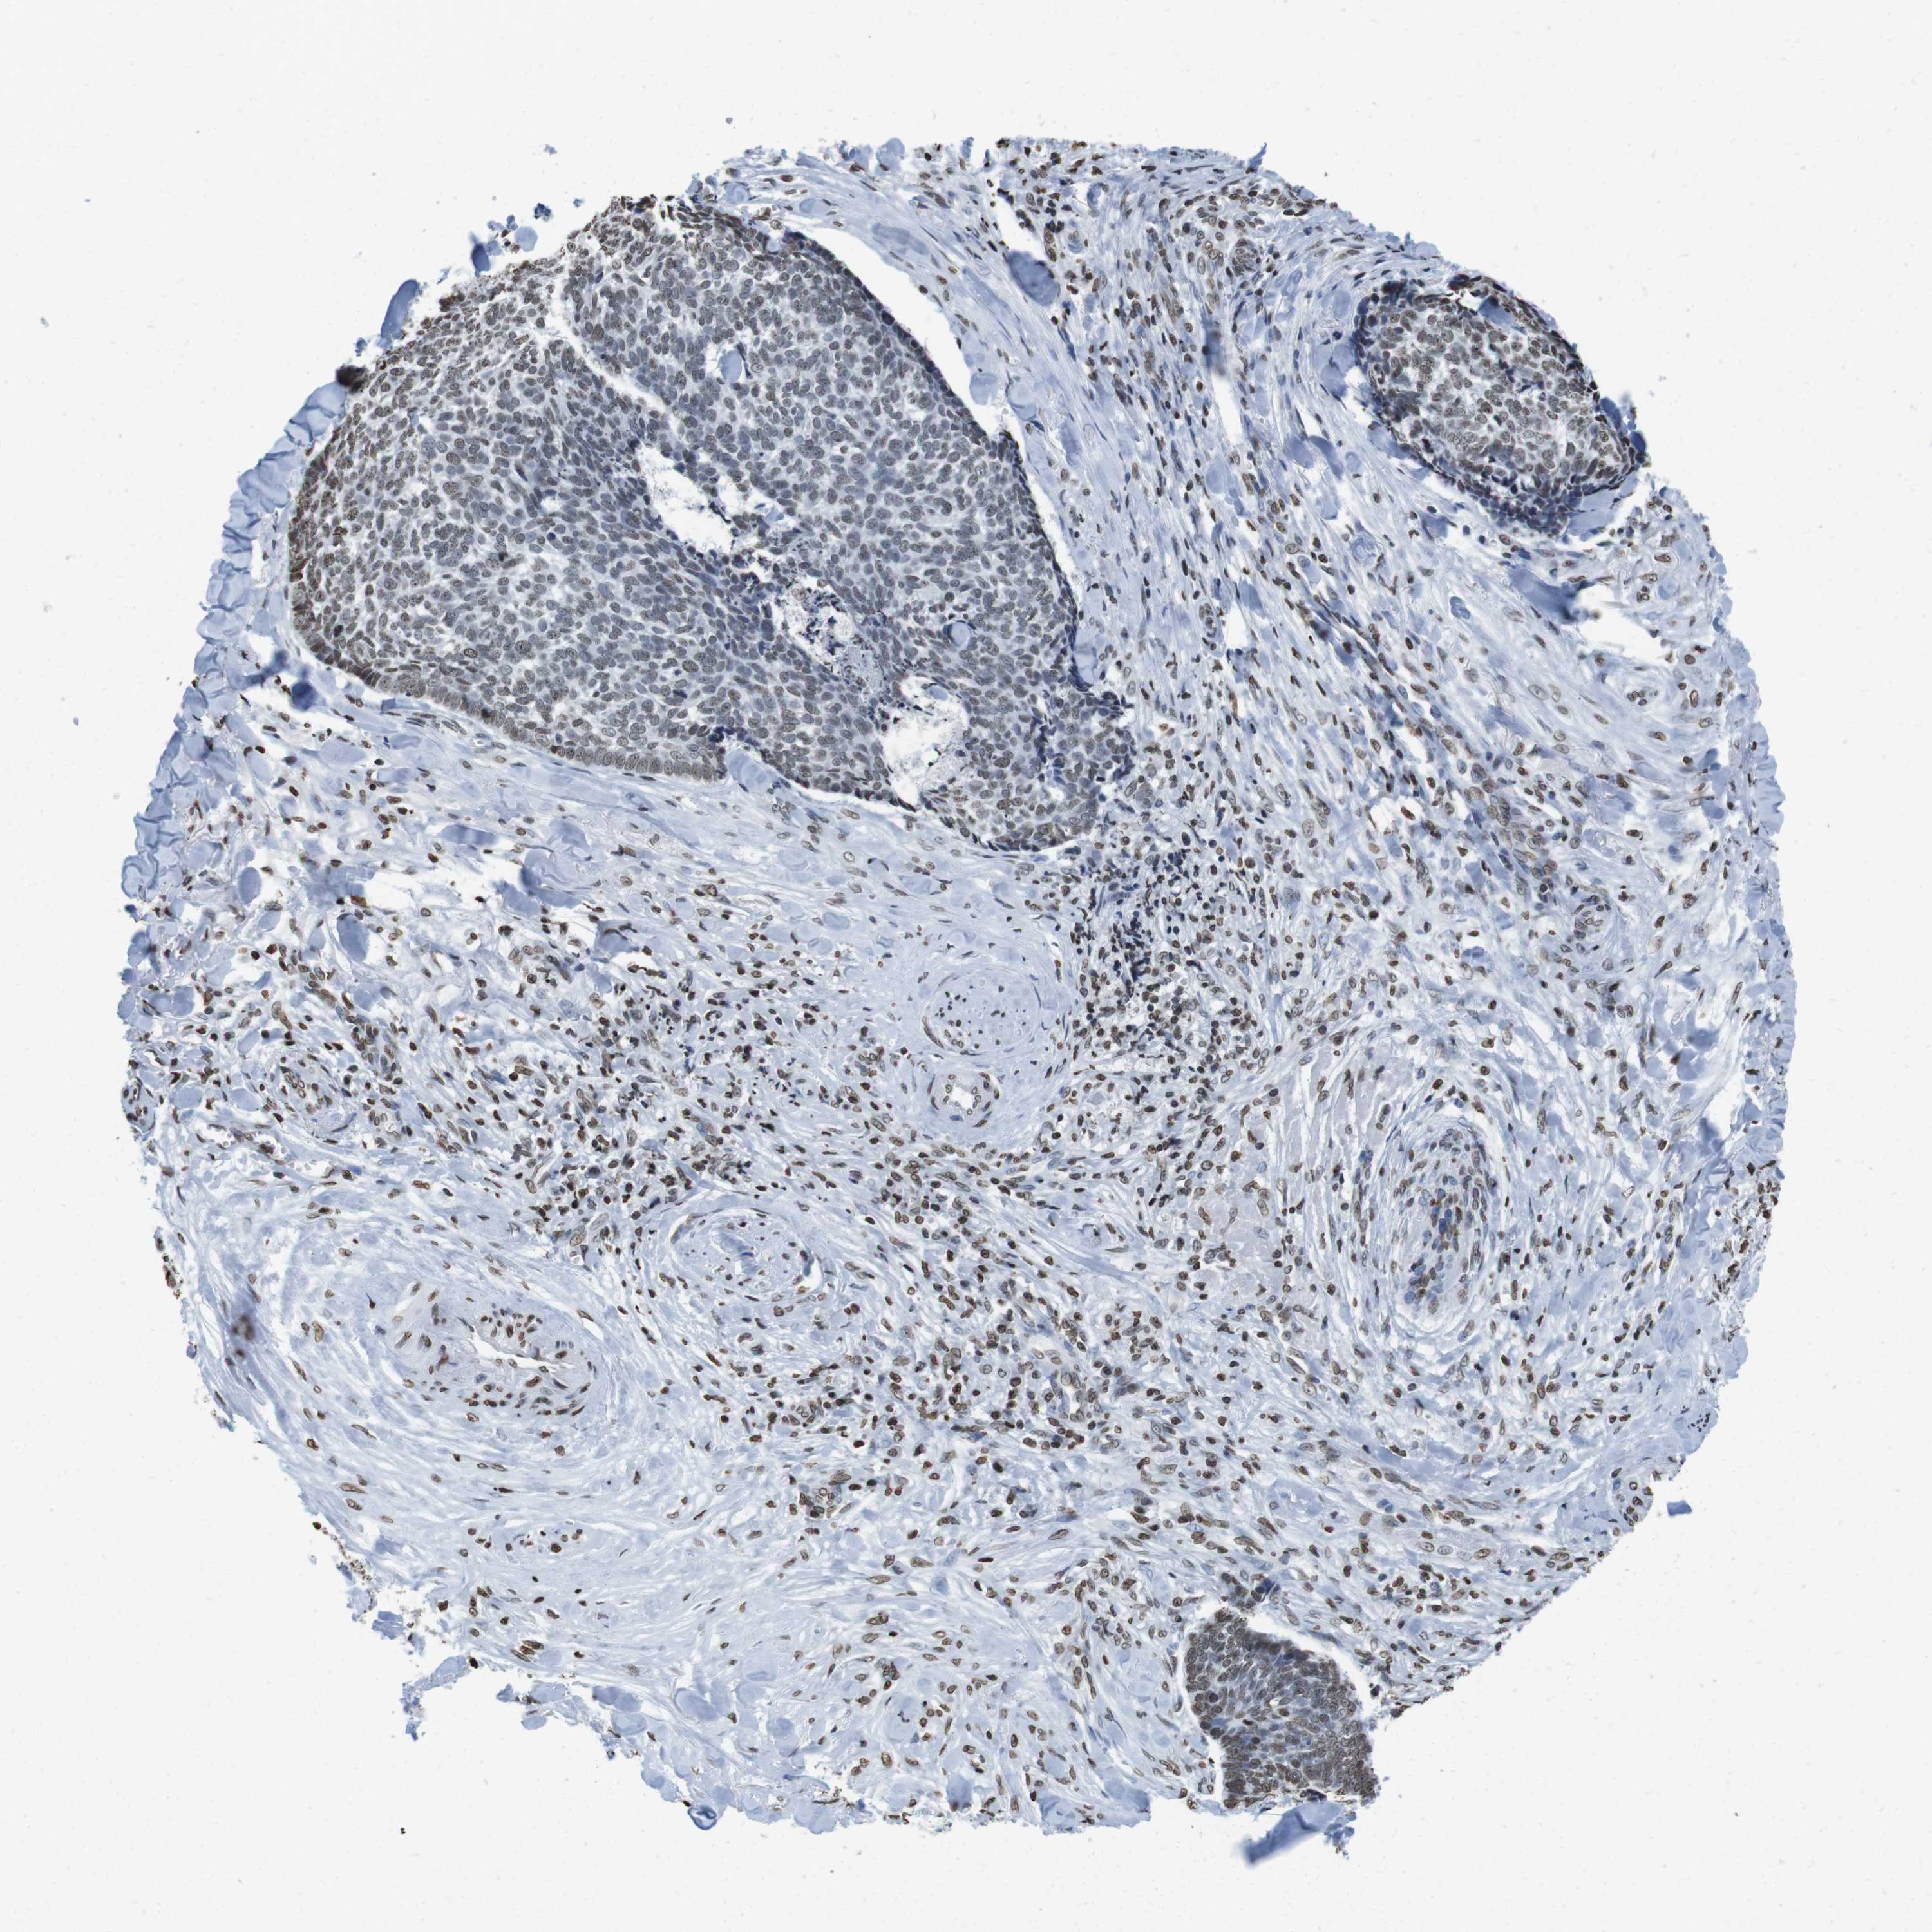

SKIN CANCER - Protein expressioni

A mouse-over function shows sample information and annotation data. Click on an image to view it in a full screen mode. Samples can be filtered based on level of antibody staining by selecting one or several of the following categories: high, medium, low and not detected. The assay and annotation is described here.

Antibody stainingi

Antibody staining in the annotated cell types in the current human tissue is reported as not detected, low, medium, or high, based on conventional immunohistochemistry profiling in selected tissues. This score is based on the combination of the staining intensity and fraction of stained cells.

Each image is clickable and will lead to virtual microscopy that enables deeper exploration of all samples and also displays staining intensity scores, fraction scores and subcellular localization as well as patient and tissue information for each sample.

Antibody HPA015654

Staining

High

Intensity

Strong

Quantity

>75%

Location

Nuclear

Squamous cell carcinoma in situ, NOS

Squamous cell carcinoma, NOS

Basal cell carcinoma

Adnexal tumor, benign